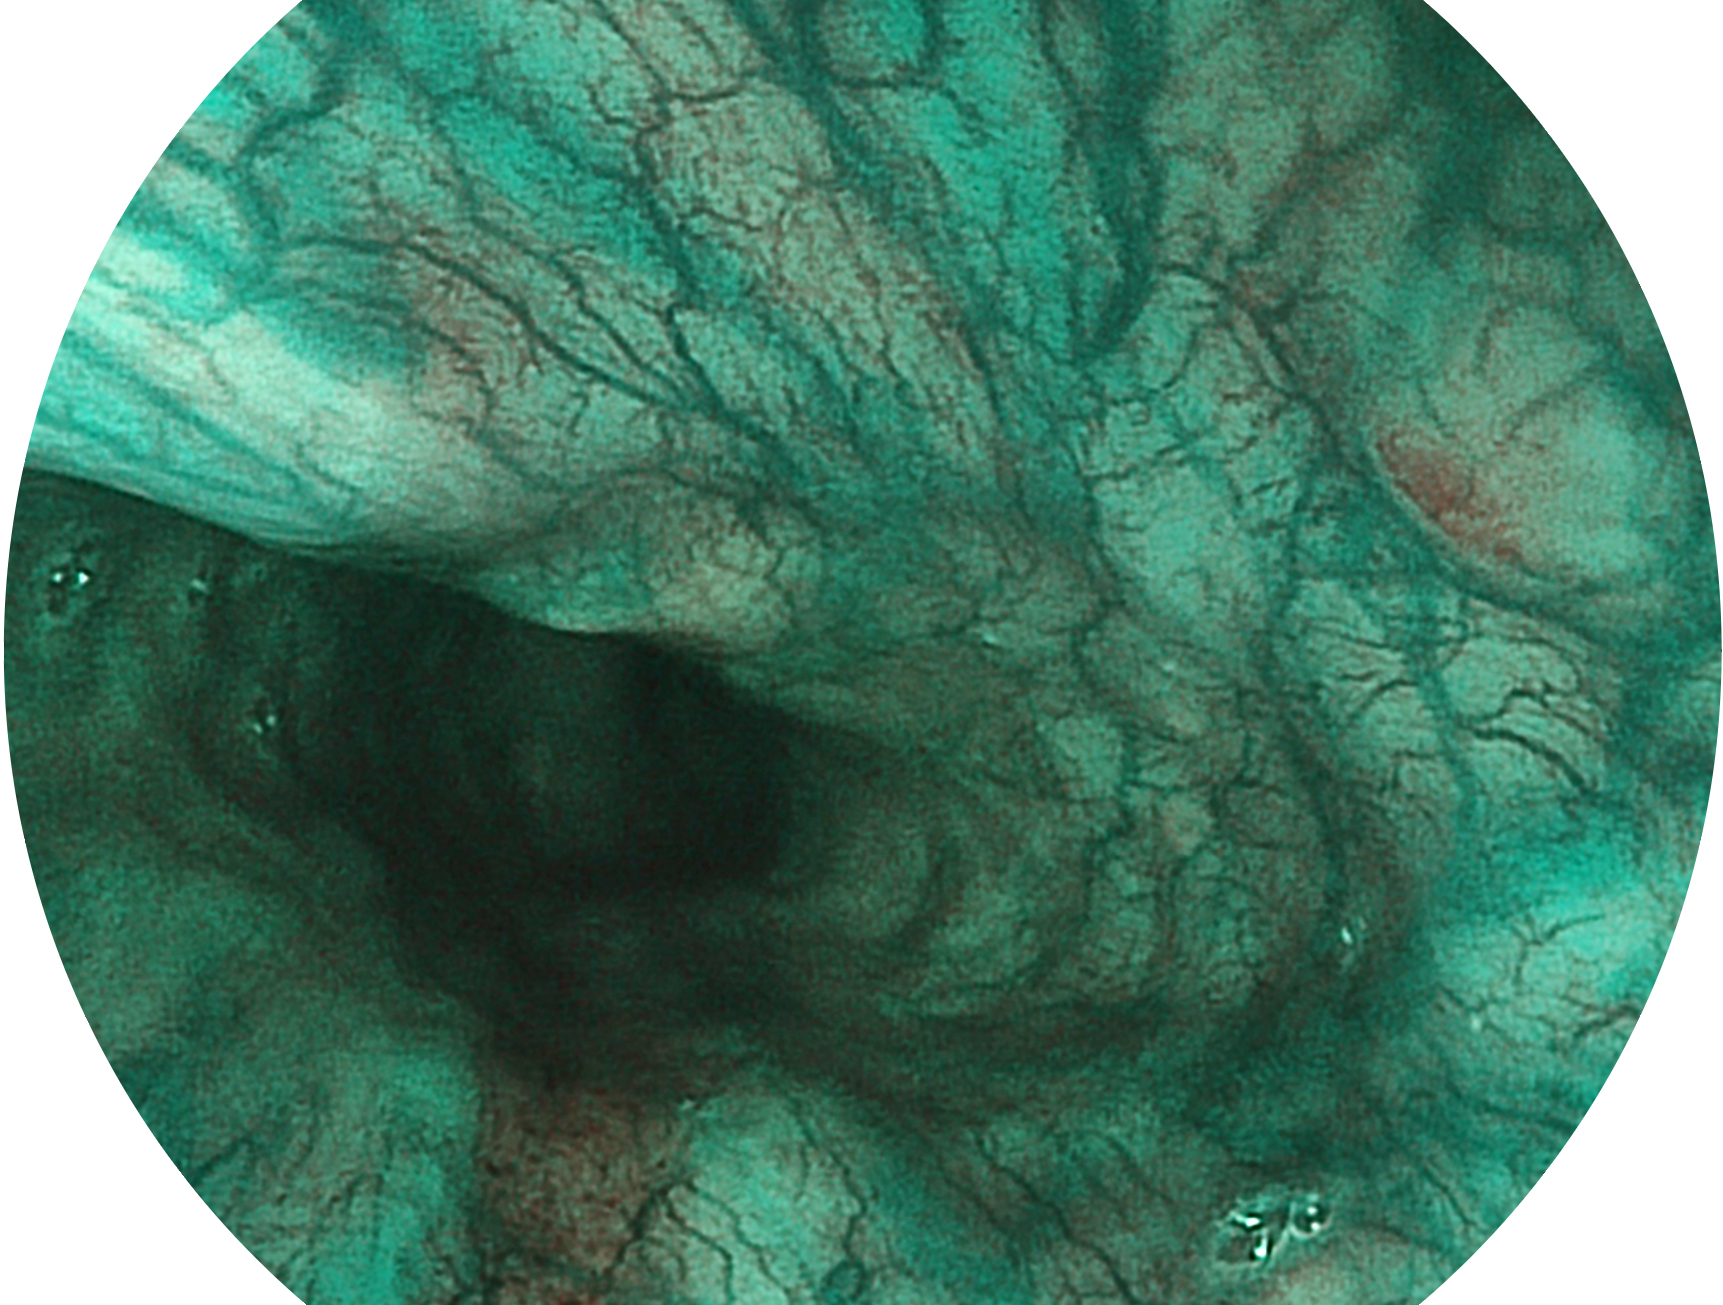

九州酷游新开发的内镜染色技术,主要是基于多波长LED 光源的开发,VLS-55Q 四波长LED 光源是由四个不同颜色的LED光按照相应照明模式所规定的特定发光比例进行合束后形成,合束后形成的照明光的光谱由红光、绿光、蓝光及蓝紫光这四个不同的波段范围构成。具有更高光谱自由度,通过光谱比例的控制,实现了聚谱成像技术,英文全称为“Spectral Focused Imaging, SFI”,缩写为“SFI”和光电复合染色成像技术,英文全称为“Versatile Intelligent Staining Technology, VIST”,缩写为“VIST”。